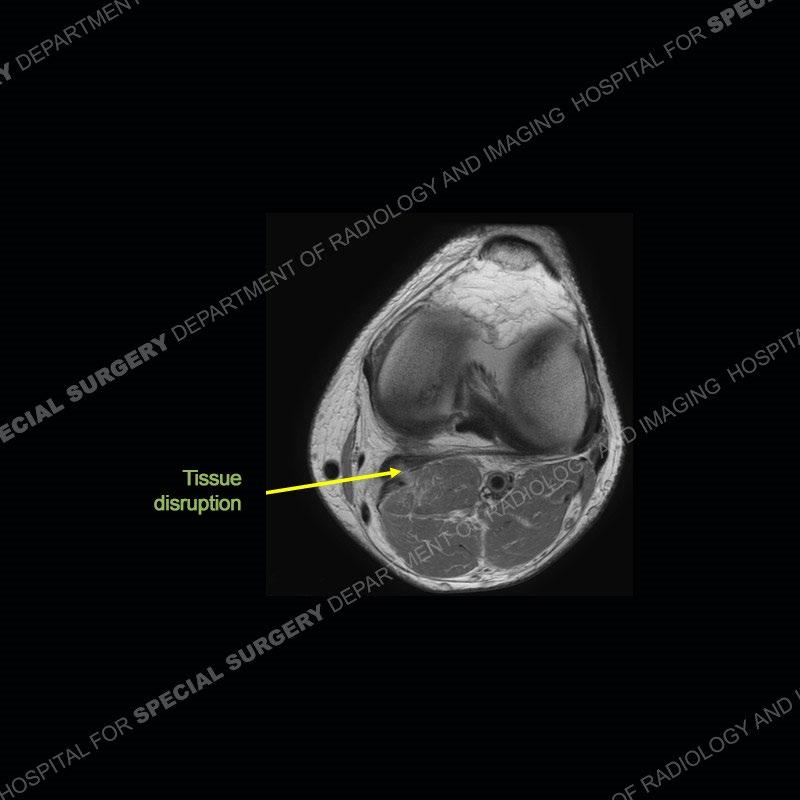

Findings

The radiographs show degenerative change of the medial compartment and a varus knee, but they are not germane to this case. No acute bony injury is present. The MRI shows edema of the posterior medial knee/soft tissue and a focal area of a partially disrupted low signal structure. The details are kept at a minimum in the findings of this case on purpose.

Diagnosis: Partial Disruption Medial Head Gastrocnemius (MHG)

The findings were kept purposefully vague as identifying the structures early on takes away a lot of the diagnosis. An uncommon entity and one of which we do not see a lot. Enthesopathic changes and tendinosis are seen as are distal MHG injuries, but proximal tears are rarely present. This case highlights a number of points. One, it almost always comes down to anatomy. Perhaps not a structure we normally spend too much time on, except save for diagnosing a Baker’s cyst, but knowing where this structure and all structures exist in all three planes is imperative. Second, when you think you are making a “call” or finding that you have never made before, step back and think is this just the abnormal presentation of a common pathology. That situation arises much more frequently. Third, if you look at it once, twice, and probably a third time and are confident in your odd or very rare diagnosis, stick to your guns. Especially, when it comes down to anatomic structures, the proof will be in the images.

Fourth, use all imaging planes and different pulse sequences to make your diagnosis. The edema highlighted in this case can be seen as the obscuration of fat on the PD images but is much easier to perceive as the high signal on the IR pulse sequences. The actual disruption of the MHG myotendinous junction is only able to be seen on the axial images. On the sagittal and coronal images, we get a sense something is wrong but hard to be exact. Lastly, when you look at a study and something just seems off (as I would say the sagittal and coronal images do with that dark band of tissue posteriorly), listen to yourself and go through the study slowly and meticulously. Most of the time you will find you were right, and something indeed is present.